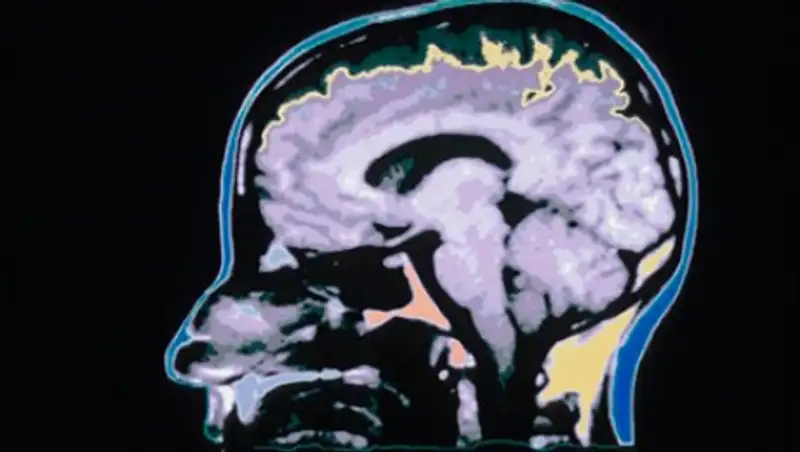

Нейробиологи из Университета Северной Каролины обнаружили цепи из нейронных клеток, которые могут отвечать за пагубную страсть к спиртному. Эти цепи объединяют две области мозга - расширенную миндалину и вентральную область покрышки, которые отвечают за реакцию на стресс и зависимости соответственно. Исследование опубликовано в журнале Biological Psychiatry.

Ранние работы уже продемонстрировали участие расширенной миндалины и вентральной области покрышки (ВОП) в проявлении алкогольной зависимости, однако впервые нейробиологам удалось продемонстрировать, что эти две области взаимодействуют друг с другом с помощью нейронной схемы. Эти сети состоят из проекционных нейронов - нервных клеток с длинными аксонами, способными передавать сигналы в другие зоны мозга.

Данные проекционные нейроны вырабатывают кортикотропин-рилизинг-гормоны (CRF), которые регулируют синтез других гормонов и участвуют в борьбе со стрессом. Эксперименты на мышах показали, что подавление активности цепей между двумя областями мозга защищает от переедания и употребления алкоголя. Таким образом, CRF-система оказалась связанной с возникновением алкоголизма.

Расширенная миндалина задействована в реакции на такой психологический стресс, как потеря работы или любимого человека, а ВОП участвует в получении удовольствия от еды, наркотических веществ и алкоголя. Ученые показали, что алкоголь активирует CRF-нейроны в расширенной миндалине, которые передают возбуждение ВОП и, в конечном итоге, способствуют дальнейшему употреблению спиртного.